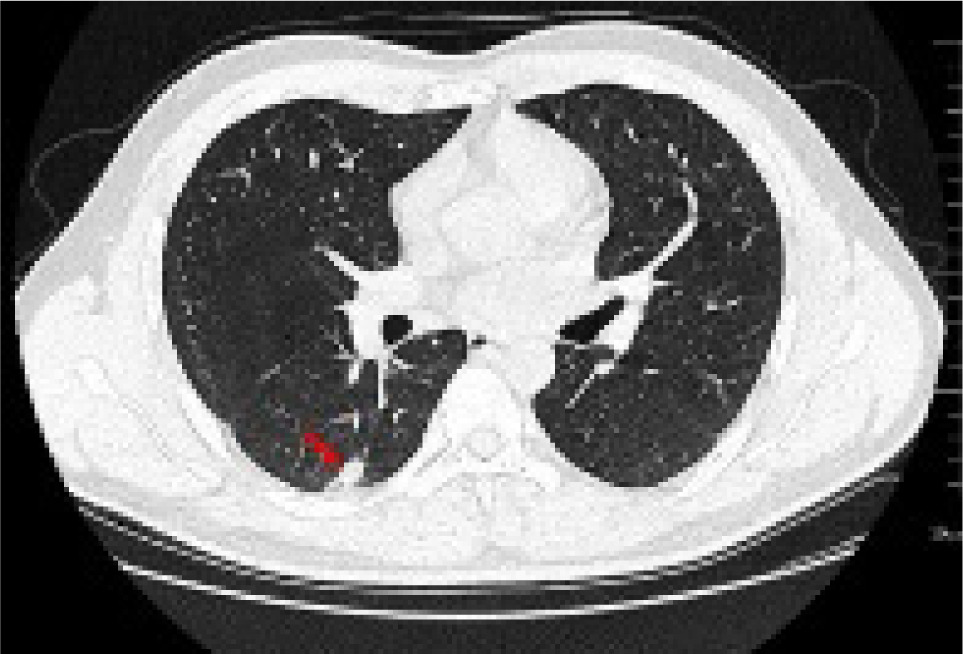

Further examinations were conducted upon admission (Table 1). A chest CAT (CT) scan conducted on January 15, 2021 suggested a possible pulmonary infection with a shadow measuring approximately 19×9 mm in the right lower lobe (Figure 1).

Figure 1: Lung CT shows that there is a calabash type density increase in the dorsal segment of the lower lobe of the right lung, the size of which was about 19×9 mm (red arrow).

Full abdominal CT and lung CT revealed a high-risk pulmonary nodule in the right lower lobe (Figure 4), pancreatic enlargement with multiple cystic lesions, and multiple ill-defined low-density lesions in both kidneys (Figure 5).

Figure 4: Lung CAT (CT) shows a ground glass nodule (12×9 mm) in the posterior basal segment of the right lower lobe (IM51), with signs of pleural depression (red arrow).